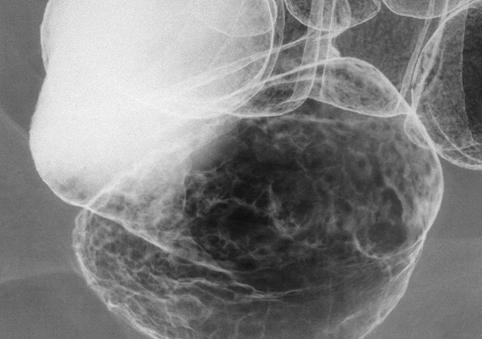

疾病(病理主体)的分类恶性上皮性肿瘤/腺癌

部位(按器官分)大肠/直肠

检查方法X线

肿瘤的肉眼分类0型(表在型)/其他

肿瘤最大直径40以上

肿瘤的深度m